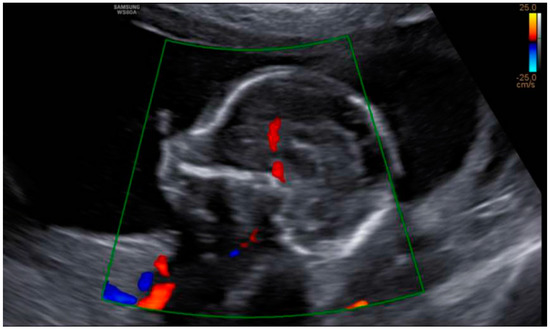

3. Results: Case Presentation

| Cardiopathy | 6% | No | No |